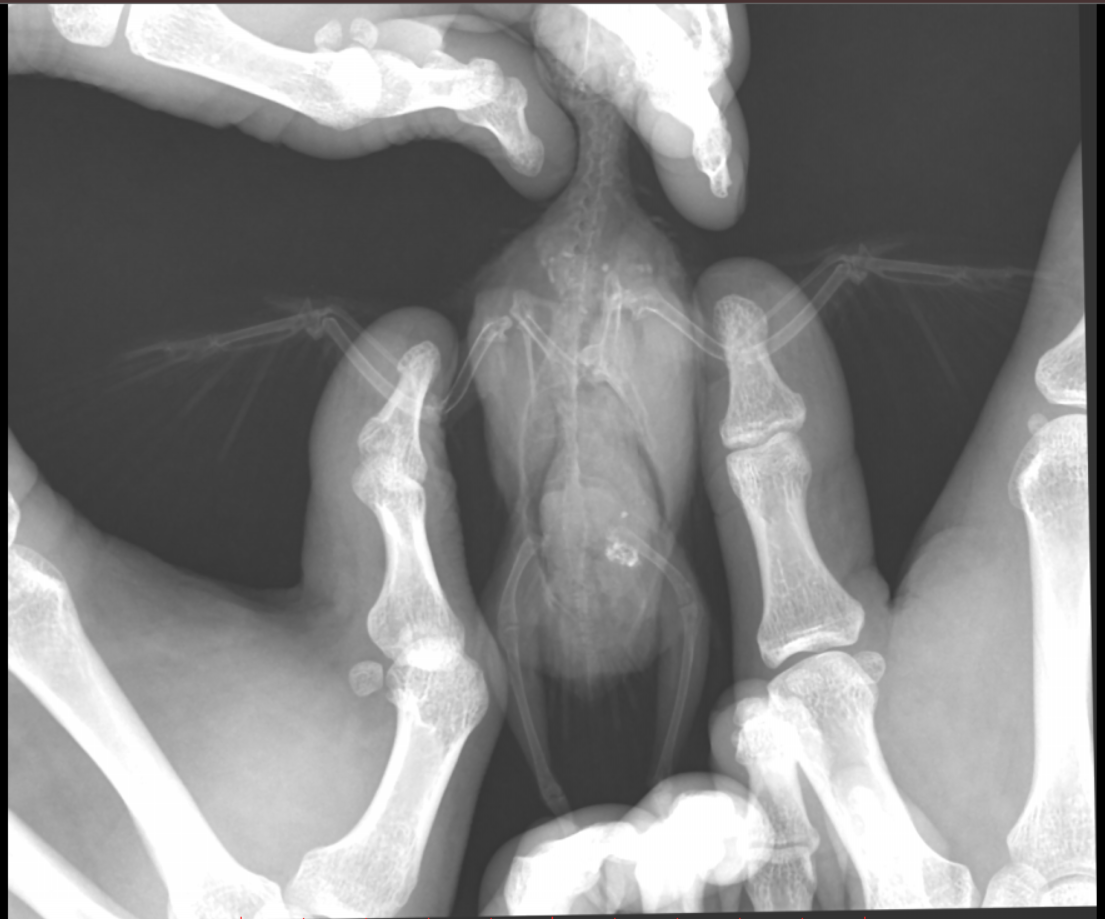

Во вторник отвозила птицу на рентген. Врач сказала, что очень сильно увеличена печень и другие органы. Также сдавлены воздухоносные мешки (из-за увеличенных внутренних органов). Отсюда - одышка. Также врач нашла перелом (старый?) ключицы. Попугая было очень сложно удерживать, поэтому снимки получились, возможно, недостаточно информативными - но какие уж получились((

@Zosia здравствуйте! Посмотрите, пожалуйста, снимки - видите ли вы на них отклонения, опухоли? Есть ли какие-то патологии? И одобряете ли вы назначенное лечение в нашей ситуации? Спасибо!

2.jpg

4.jpg

Печень видится мне увеличенной, но нужно чтобы @Zosia достоверно прочла снимки.

ответ: я увидела на снимках запущенную пневмонию, увеличенные семенники (и возможно опухоль на них), увидела в помете много палочек. Отсюда - назначение.

6.Тень семенников действительноу величена. Но снимок вами показан дурного качества. И бОльшего я сказать не могу.